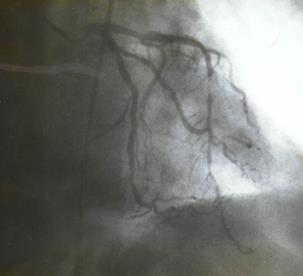

2.3.5 Коронароангиография (КГ), вентрикулография (ВГ)

Коронарографическое исследование проводили на ангиографических установках "AngioscopeD" фирмы "Siemens" (Германия), "Integris 3000" фирмы "Philips" (Голландия) по методу М. Judkins и Sones. Для контрастирования КА использовали омнипак 300-350. КГ ЛКА выполняли в стандартных проекциях по методике Gensini: правая косая 150 и 450, левая косая проекция 600, левая боковая 900. В некоторых случаях использовали дополнительные проекции: левая передняя косая 450-750, каудокраниальная 300.КГ ПКА выполняли в стандартных проекциях: правой косой 450, левой косой 600, левой боковой 900 от сагиттальной оси. Анализ коронарограмм осуществляли на просмотровом аппарате "Tagarno 35AX". При анализе коронарограмм определяли тип кровоснабжения сердца, состояние основного ствола ЛКА, степень и уровень поражения коронарных артерий, диаметр коронарных артерий, количество пораженных артерий, наличие коллатерального кровотока.

Коронарография выполнена всем больным. Всем больным выполнена ангиография левой внутренней грудной артерии.

Вентрикулография выполнена в правой косой проекции 12 пациентам. Расчет ФВ ЛЖ производили по методу В. W. Gilbert (1976).

Контрактильность оценивалась по баллам (в передне-базальном, переднелатеральном, апикальном, диафрагмальном, задне-базальном сегментах): 1 - норма, 2 - умеренный гипокинез, 3 - выраженный гипокинез, 4 — акинез, 5 — дискинез. Индекс асинергии ЛЖ измеряли по баллам в сегментах с помощью программы "Contron". В связи с малым количеством исследований мы не приводим распределения выявленных изменений у больных обеих групп.